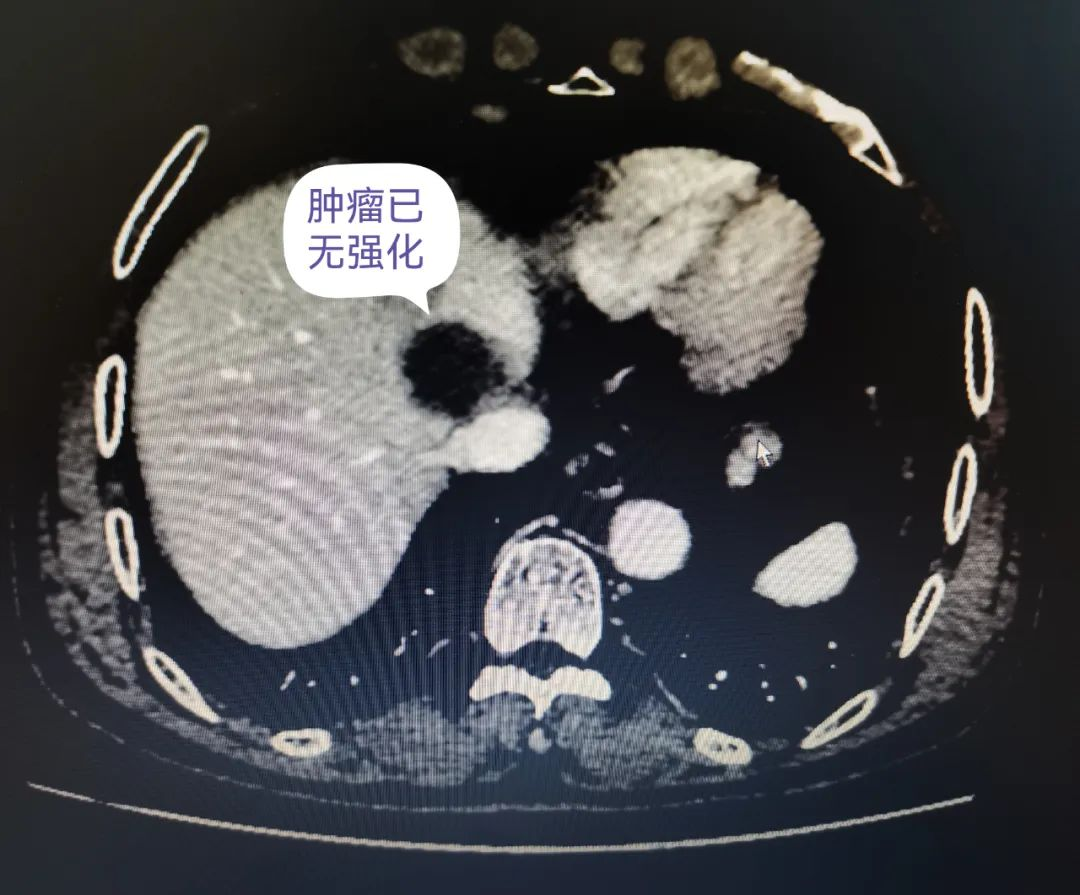

术后3周,患者复查腹部增强CT提示原第二肝门区肝细胞癌/肝中静脉癌栓及肝左叶子灶无强化,查甲胎蛋白5.4 ng/mL。目前患者继续定期免疫靶向治疗,定期复查随访。

术后3周复查增强CT提示肿瘤已无强化